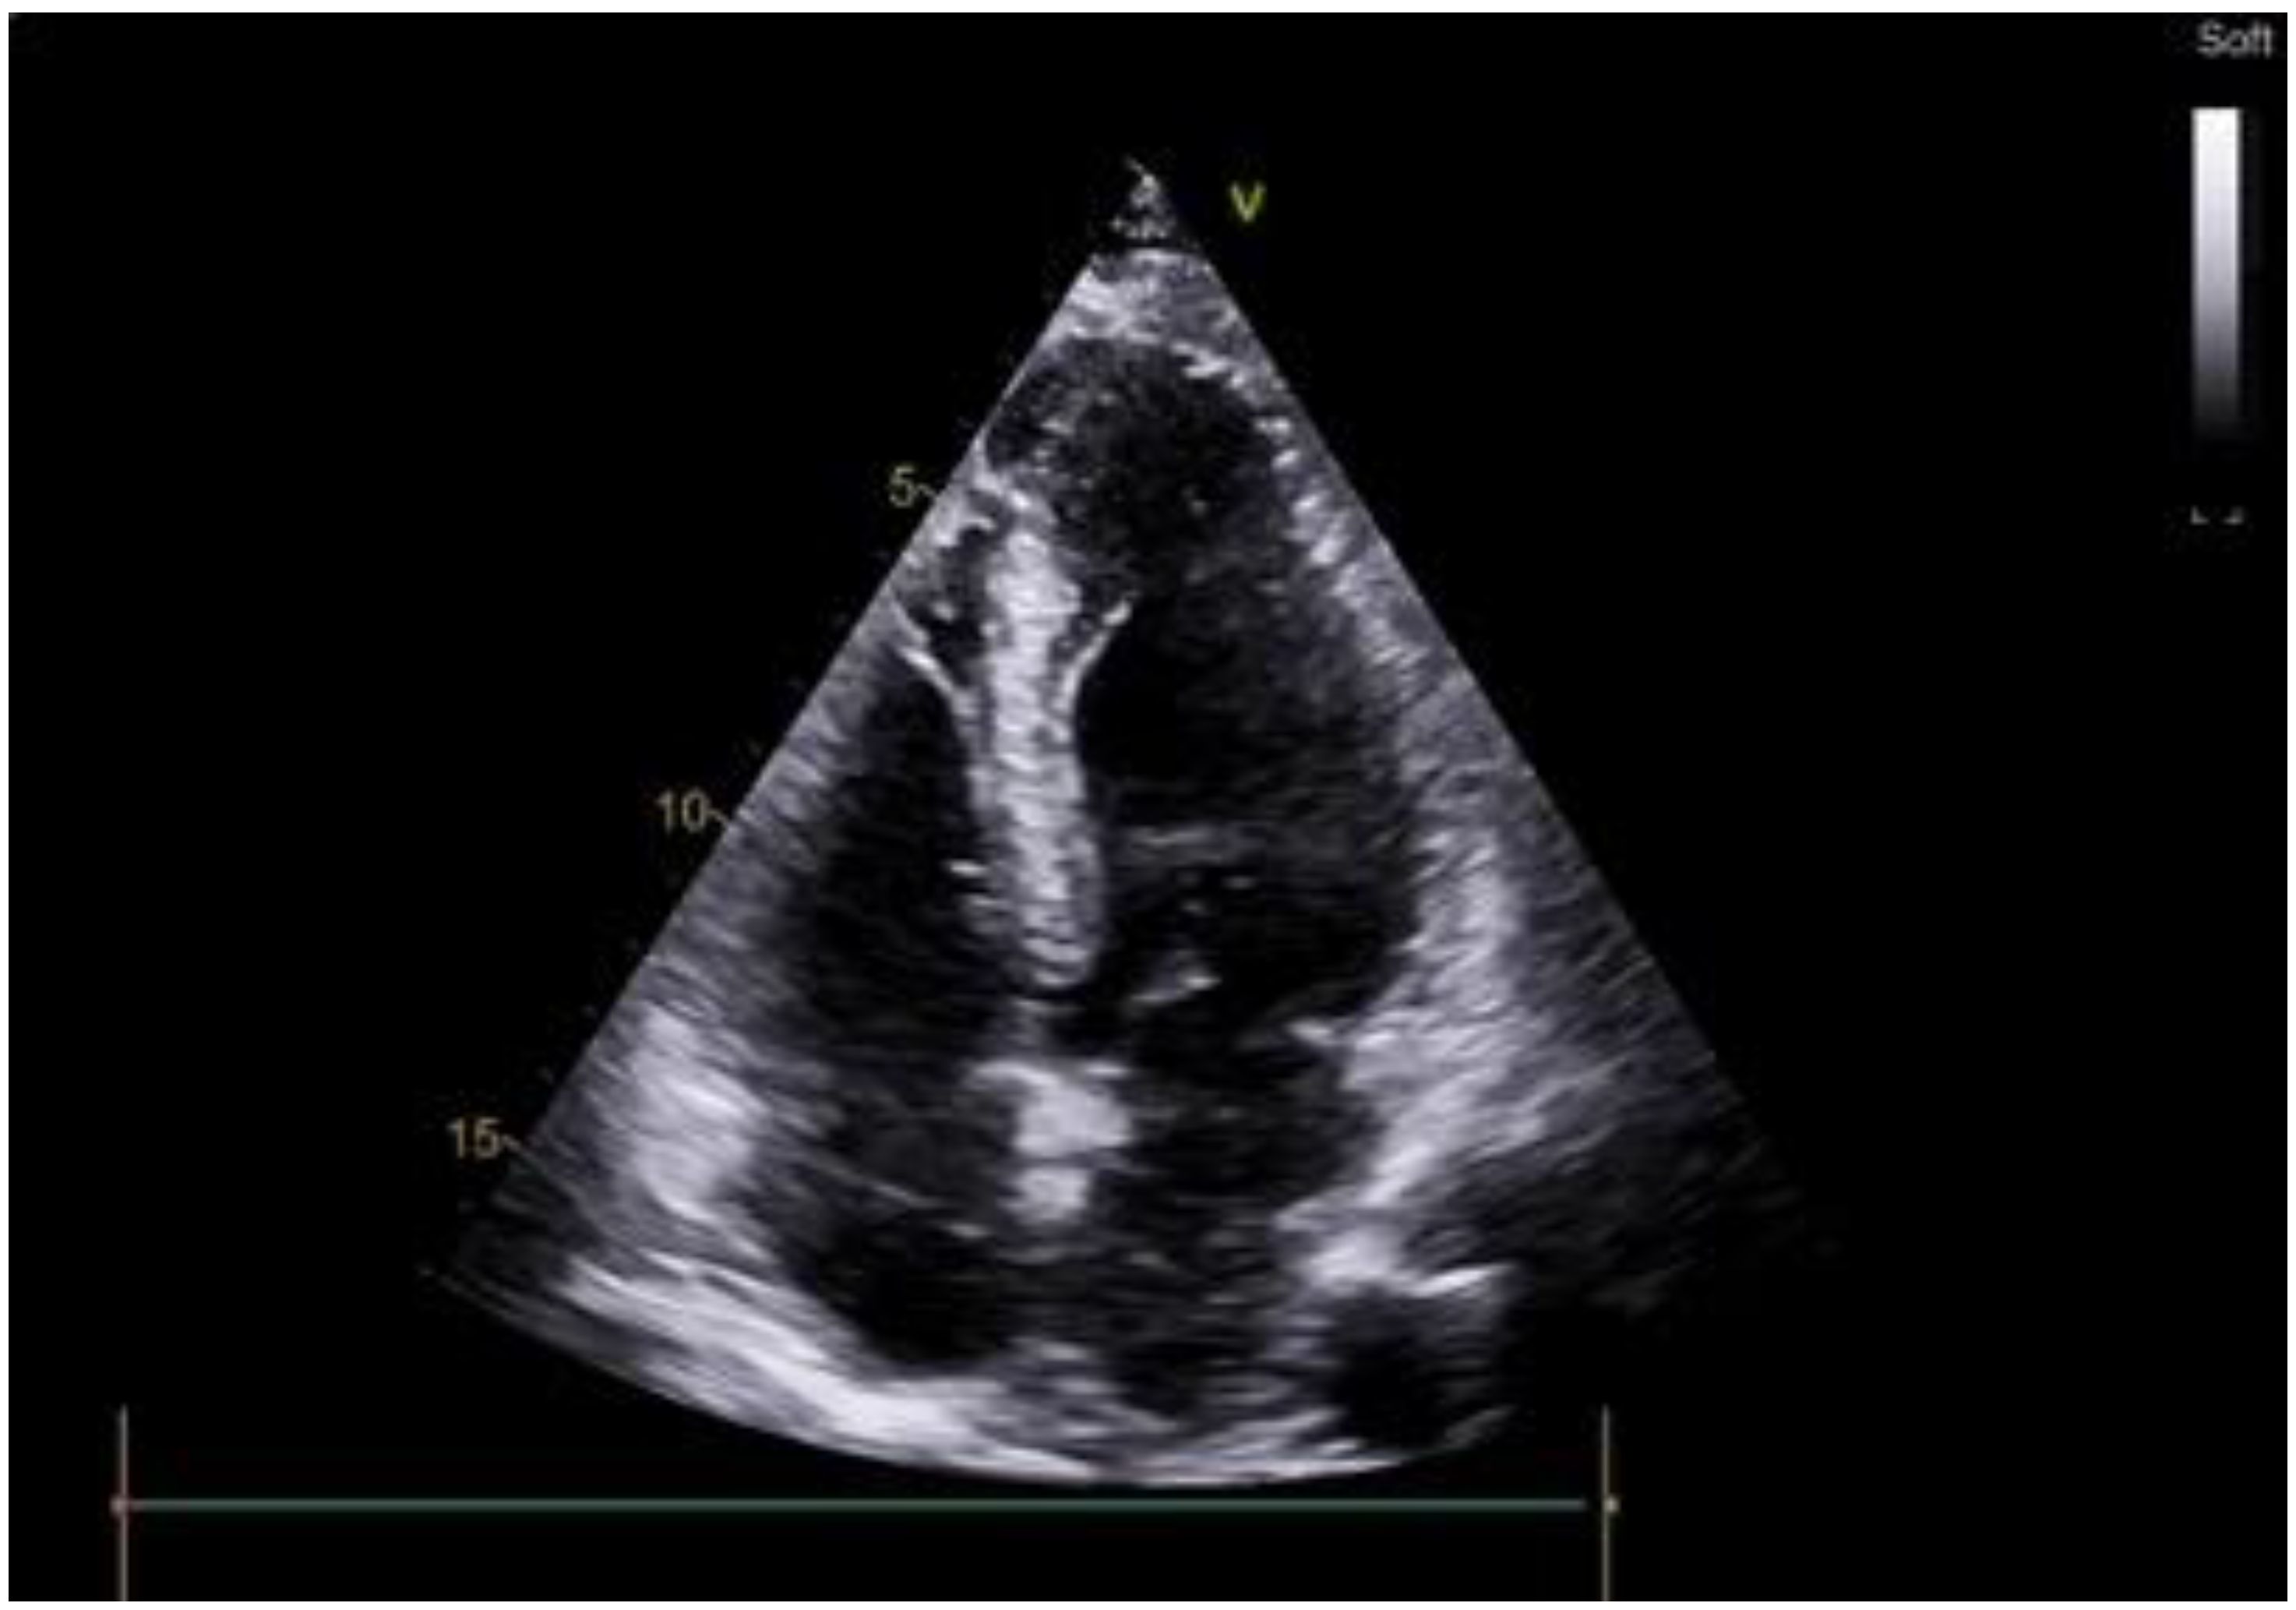

2.1. Case Scenario